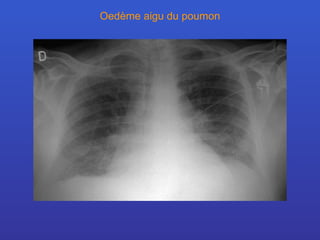

Oedème aigu du poumon